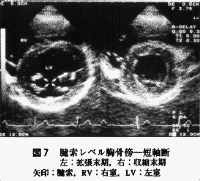

次いで徐々に探触子を心尖方向を見るように傾けていくと(左室腔が楕円とならず正円となるように必要に応じて肋間の移動も行う)、僧帽弁レベル、腱索レベル、乳頭筋レベル、心尖レベル(図6,7,8,9)と順次各レベルでの短軸断面が観察されるので2)の観察ポイントに注意しながら断面を描出していく(左室短軸断面の静止画を記録する場合は壁運動評価もある程度可能な拡張末期と収縮末期の2時相が適している)。